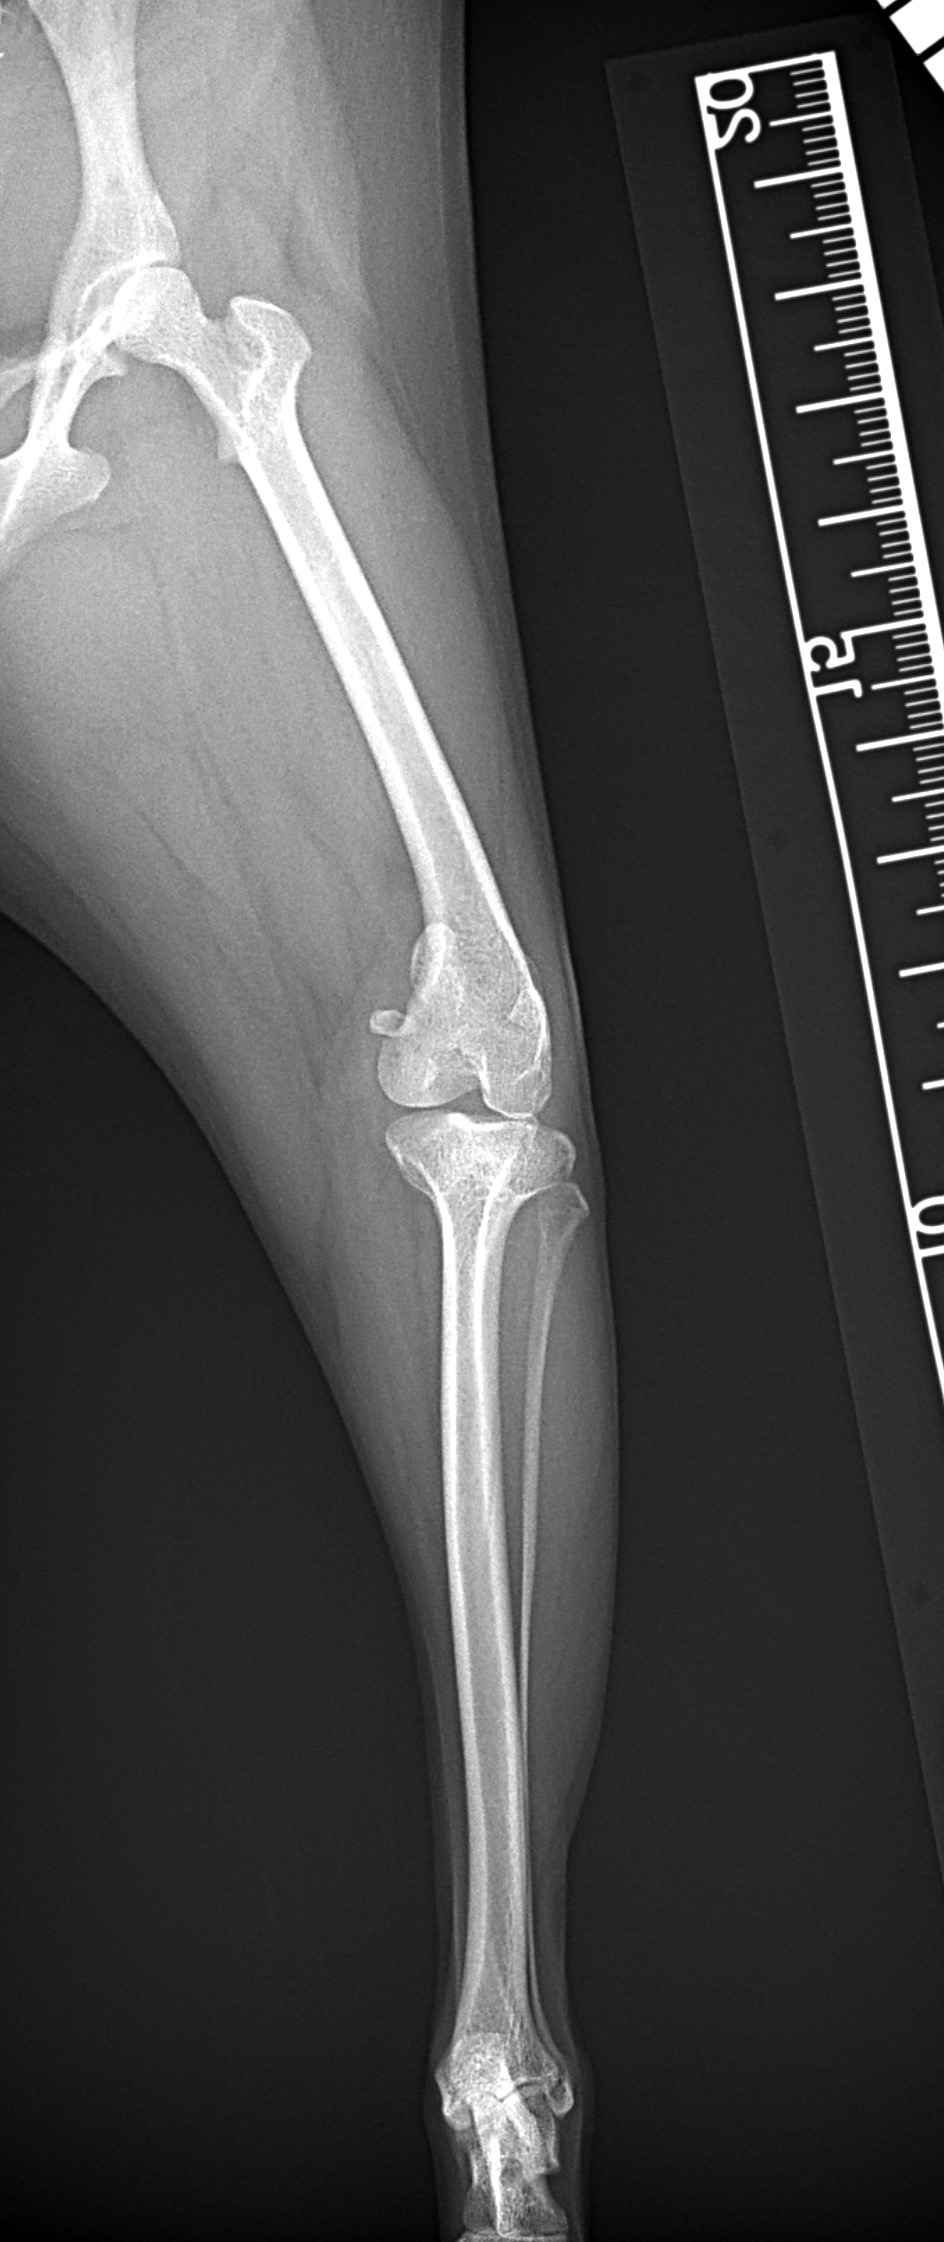

膝蓋骨内方脱臼 グレード4

小型犬の膝蓋骨内方脱臼(MPLグレード4)に対する整復依頼があった。徒手によって膝蓋骨が大腿骨滑車内に完納しない、つまり重症である。BRTにより大腿骨滑車形成術を行い、内側広筋の筋膜リリース、パテラを滑車に戻した状態で余剰関節包の再建術を実施。脛骨粗面を骨切り、大腿四頭筋〜膝蓋骨〜脛骨粗面〜足根関節のアライメント調整を行い仮固定ピンによりT.T.Tの移動幅を決定。5.0mmのスパイク形状のスペーサーでLateralizationを行った。1.5 Staggered Locking Patella Plate for T.T.Tを利用し、強固に粗面の固定術を実施。最後に骨切り部位にBRTで得られた海綿骨を移植し終了。日本ではまだ馴染みの少ない術式ではあるが、ドイツを中心にヨーロッパにおいて認知されはじめている。